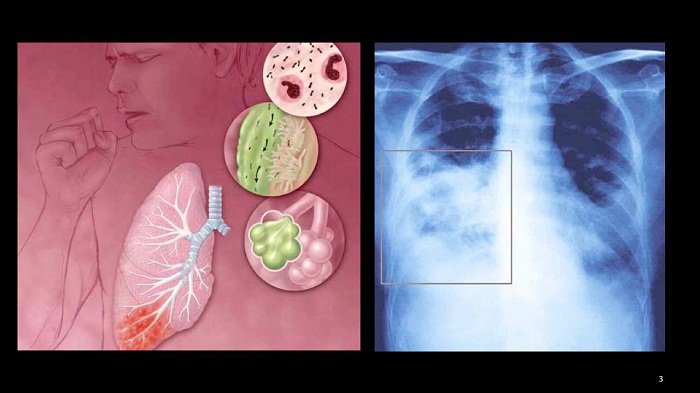

Virus RSV - Nguyên nhân gây bệnh viêm phổi ở trẻ em

Virus RSV (virus hợp bào hô hấp) là một trong những nguyên nhân thường gặp gây bệnh đường hô hấp (viêm tiểu phế quản, viêm phổi) ở trẻ em. Hiện chưa có vắc-xin phòng ngừa virus RSV và thuốc điều trị đặc hiệu nên việc phát hiện bệnh sớm để có kế hoạch điều trị và chăm sóc kịp thời là rất quan trọng.